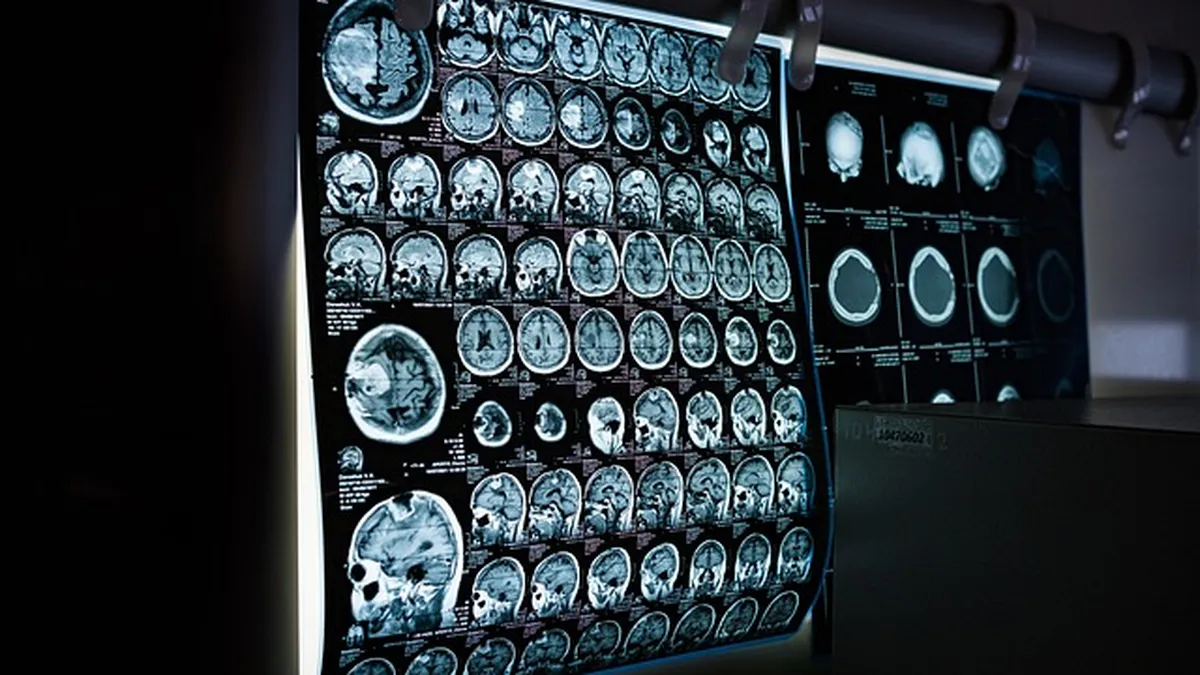

Un estudio reciente, publicado en European Archives of Psychiatry and Clinical Neuroscience, sugiere que los rasgos psicopáticos pueden identificarse mediante cambios estructurales en el cerebro detectados a través de resonancias magnéticas.

La investigación, liderada por el Instituto de Medicina del Cerebro en Jülich y la Universidad RWTH Aachen (Alemania), analizó las imágenes cerebrales de 39 hombres con altos niveles de psicopatía y las comparó con un grupo de control. Los resultados revelaron diferencias significativas que vinculan los comportamientos antisociales con modificaciones cerebrales específicas.

Mediante una técnica llamada morfometría basada en deformaciones, los científicos calcularon el volumen cerebral de los participantes. Los resultados mostraron que las personas con rasgos psicopáticos presentaban una reducción del 1,45 % en el volumen total del cerebro frente al grupo control. Aunque esta cifra parezca pequeña, es significativa en neurociencia.